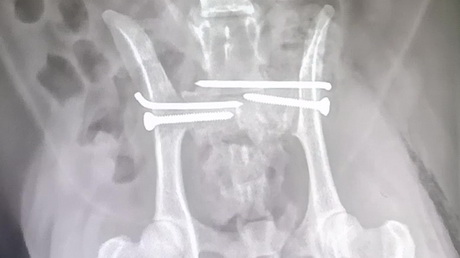

A surgical pelvic fracture in a cat

Play this video

16 Dec 2019

(Duration 04:12)